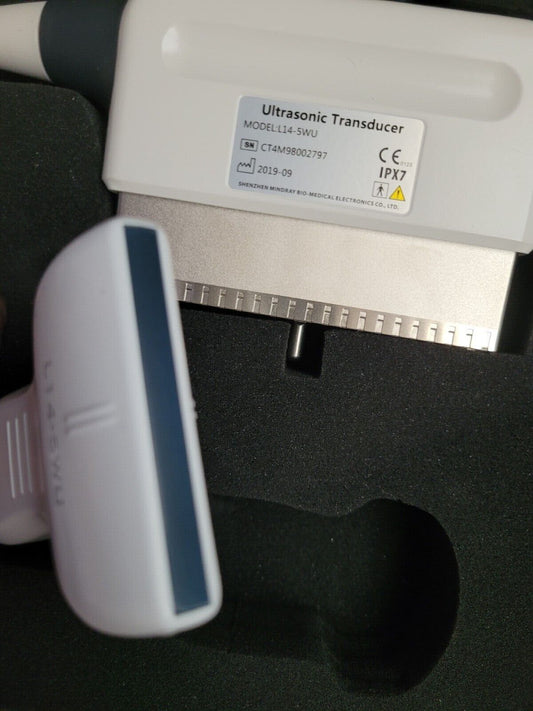

Mindray L14-5WU Linear Ultrasound Probe for Resona 7 (Demo Probe)

Regular price $999.00 USDRegular priceUnit price / per -